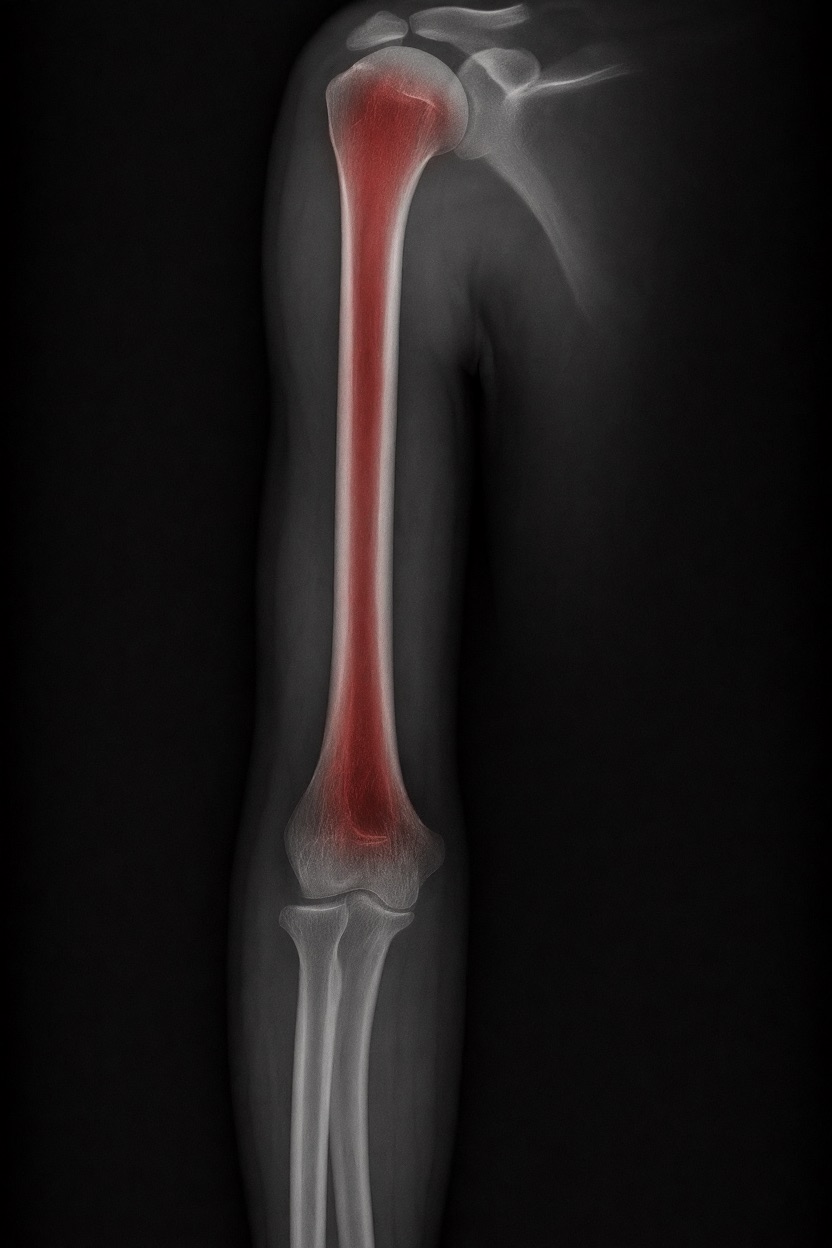

友人が提案した、気取らない実験:

アートや写真の編集用に設計されたFlux Kontextのようなモデルを、医療画像、たとえば「単純な」骨折の赤色マーキングに使用できるか?

即答:面白い結果を出すが、過剰に反応し、医療ツールとしては信頼性に欠ける。これはアイデアを試すためのプロトタイプに過ぎない。

Civitai用に作成した、100% AI生成の合成ミニデータセット(健康なX線10枚、骨折のあるX線10枚)でテスト:

- 健康な骨での偽陽性:100%

- 骨折検出:≈ 45%